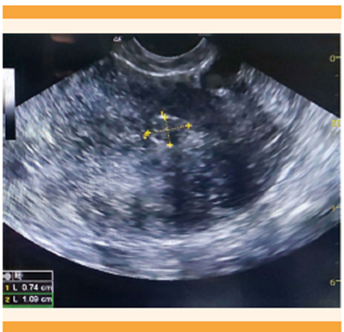

Las hormonas sexuales esteroideas tienen un papel importante en la patogenia del leiomioma. De igual manera, se ha encontrado una asociación etiológica con la desregulación de las vías de señalización celular, expresión de micro-ARN y anomalías citogenéticas. 28 Los factores de riesgo de leiomiomatosis son: edad, raza, hormonas endógenas y exógenas, obesidad, infección uterina y el estilo de vida, como la dieta, el consumo de cafeína y alcohol, actividad física, estrés y tabaquismo; no obstante, algunos de este último grupo no están definidos claramente. 32 El diagnóstico se establece mediante ecografía, mientras que la resonancia magnética se reserva, principalmente, para las pacientes con cuatro o más masas. 33 Figuras 7y8